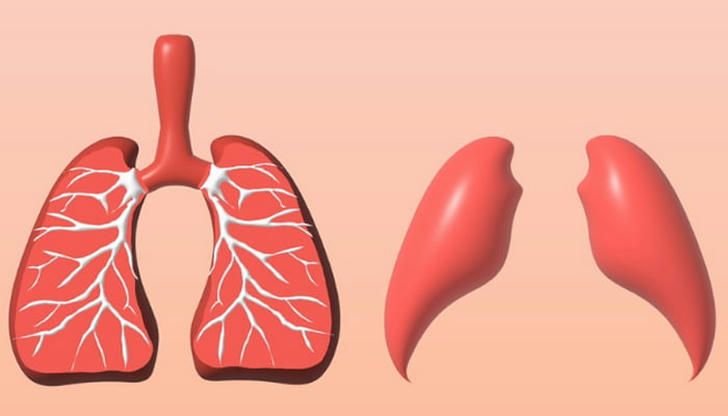

Which procedure involves surgically removing a lobe of the lung?

Correct Incorrect A lobectomy is a surgical procedure that involves removing an entire lobe of the lung, often to treat conditions like lung cancer. The goal is to remove the affected lobe to restore normal lung function. The right upper lobectomy is one of the most frequently performed types of this surgery.